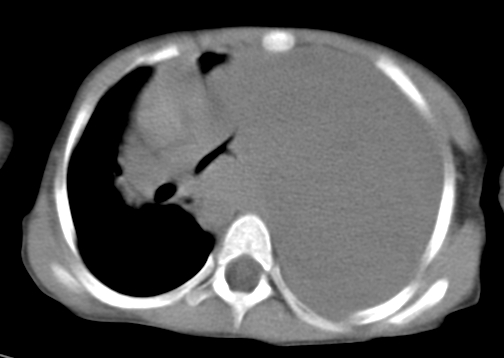

患儿 女 4岁,发热 咳嗽 胸透 考虑:左侧脓胸

左侧胸廓内见大量密实阴影,肺尖部尚有少量肺组织影,纵膈明显受压移位,肋骨未见明显受侵征象,虽然病人年龄较小,但如此大量的“积液”,还是要警惕,不同意一般感染,可结合穿刺脱落细胞学检查。

左侧大量胸腔积液。

左侧大量胸腔积液;建议胸水检查。

左侧大量胸腔积液,原因待查。